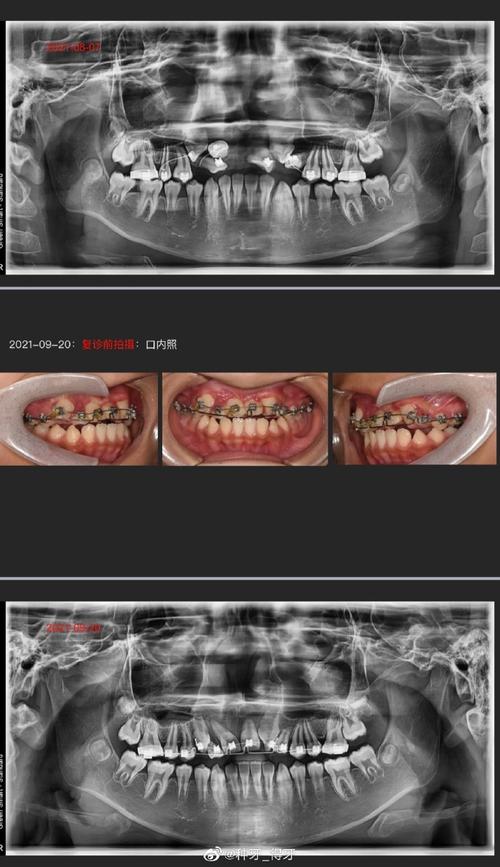

牙齿并非孤立存在,其下方有牙根(牙体组织的主要支撑结构),周围包裹着牙槽骨(固定牙齿的骨骼),拍片(如根尖片、全景片)能清晰显示牙根的形态、长度、是否有弯曲、吸收或断裂,以及牙根间是否存在骨间隔、囊肿或炎症,若患者牙根存在先天弯曲或过短,盲目施加矫正力可能导致牙根吸收甚至牙齿脱落;而埋伏牙(未正常萌出的牙齿)或多生牙(额外生长的牙齿),只有通过拍片才能准确定位其位置和方向,避免矫正中误伤。

牙齿的移动依赖于牙槽骨的改建(压力侧吸收、牵引侧增生),而颌骨的大小、形态直接影响矫正方案的设计,头颅侧位片能测量颌骨的长度、宽度、高度,判断是否存在“地包天”“龅牙”等骨性畸形——若骨性问题突出,可能需要配合正颌手术才能达到理想效果;全景片则可观察牙槽骨的高度和厚度,若牙槽骨因牙周病等原因吸收严重,牙齿移动时可能暴露牙根,甚至引发松动,拍片还能发现颌骨内的囊肿、肿瘤等病变,避免在矫正过程中刺激病灶。

牙周是牙齿的“土壤”,其健康状况直接决定矫正的可行性和安全性,牙周病患者常存在牙槽骨吸收、牙龈萎缩等问题,若未拍片评估就直接矫正,牙齿移动可能加速骨吸收,导致牙齿松动甚至脱落,通过拍片(如曲面断层片、CBCT),医生能判断牙周组织是否耐受矫正力,并制定分阶段治疗方案(先治疗牙周病,再开始矫正)。

| 全景片(曲面断层片) | 全口牙齿、牙根、牙槽骨、颌骨、上颌窦、下颌神经管等 | 观察牙齿数量、萌出方向、牙根形态,判断牙槽骨高度、有无囊肿/埋伏牙 |

| CBCT(锥形束CT) | 三维重建牙齿、牙根、牙槽骨、神经血管等精细结构 | 精准定位复杂病例(如埋伏牙、种植体植入),评估骨量,降低神经损伤风险 |